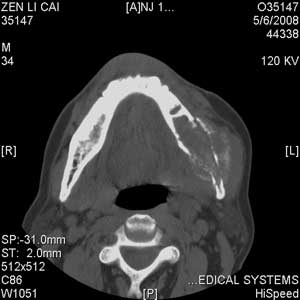

以下是引用jiangjing在2008-5-28 15:56:00的发言:[br]下颌骨左侧部骨质破坏,轻度膨胀,瘤骨形成,软组织肿胀考虑 恶性骨肿瘤-----肉瘤类